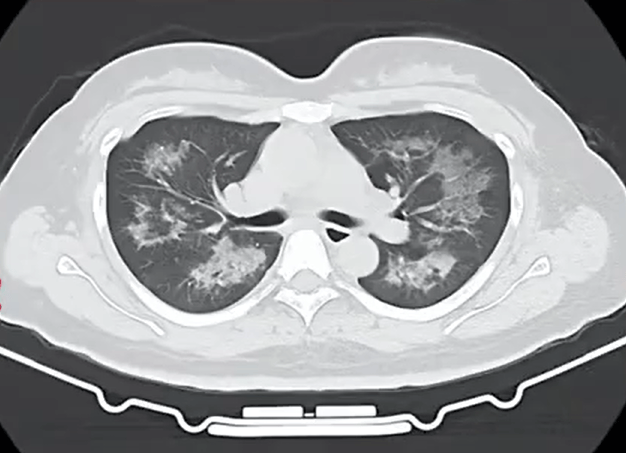

胸部CT进一步显示,她的双肺出现多发斑片状模糊影,被诊断为间质性肺炎rng虚拟币。医生判断,病因很可能与她近期长期接触的某类物质相关。经过医生反复细致地询问病史,小江才说出自己存在长期、频繁使用定妆喷雾的情况。